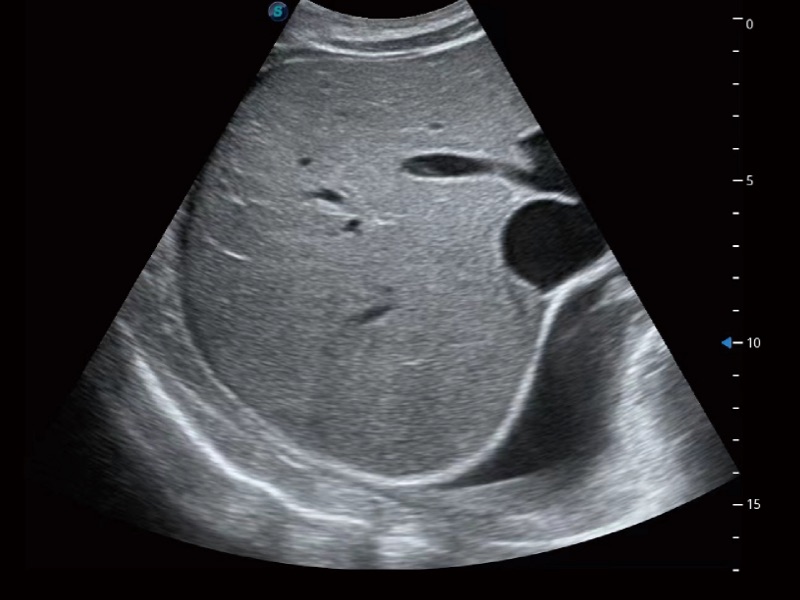

腹部应用

造影成像功能和定量分析工具包使医生能够准确的评估血流灌注情况。独特的动态声压控技术有效控制造影剂的声压,保证造影剂持续时间,方便医生观察病变灌注的延迟相位。